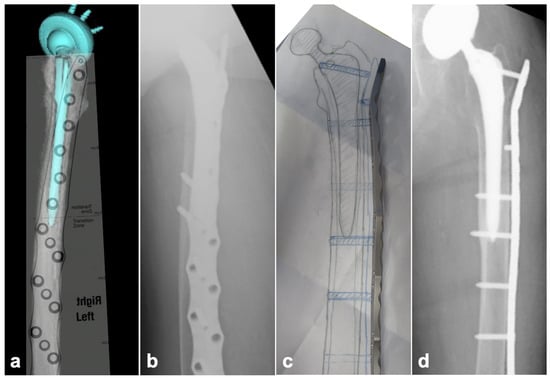

2.2. Preoperative Planning

2.3. Surgical Technique

2.3.1. BHA/THA